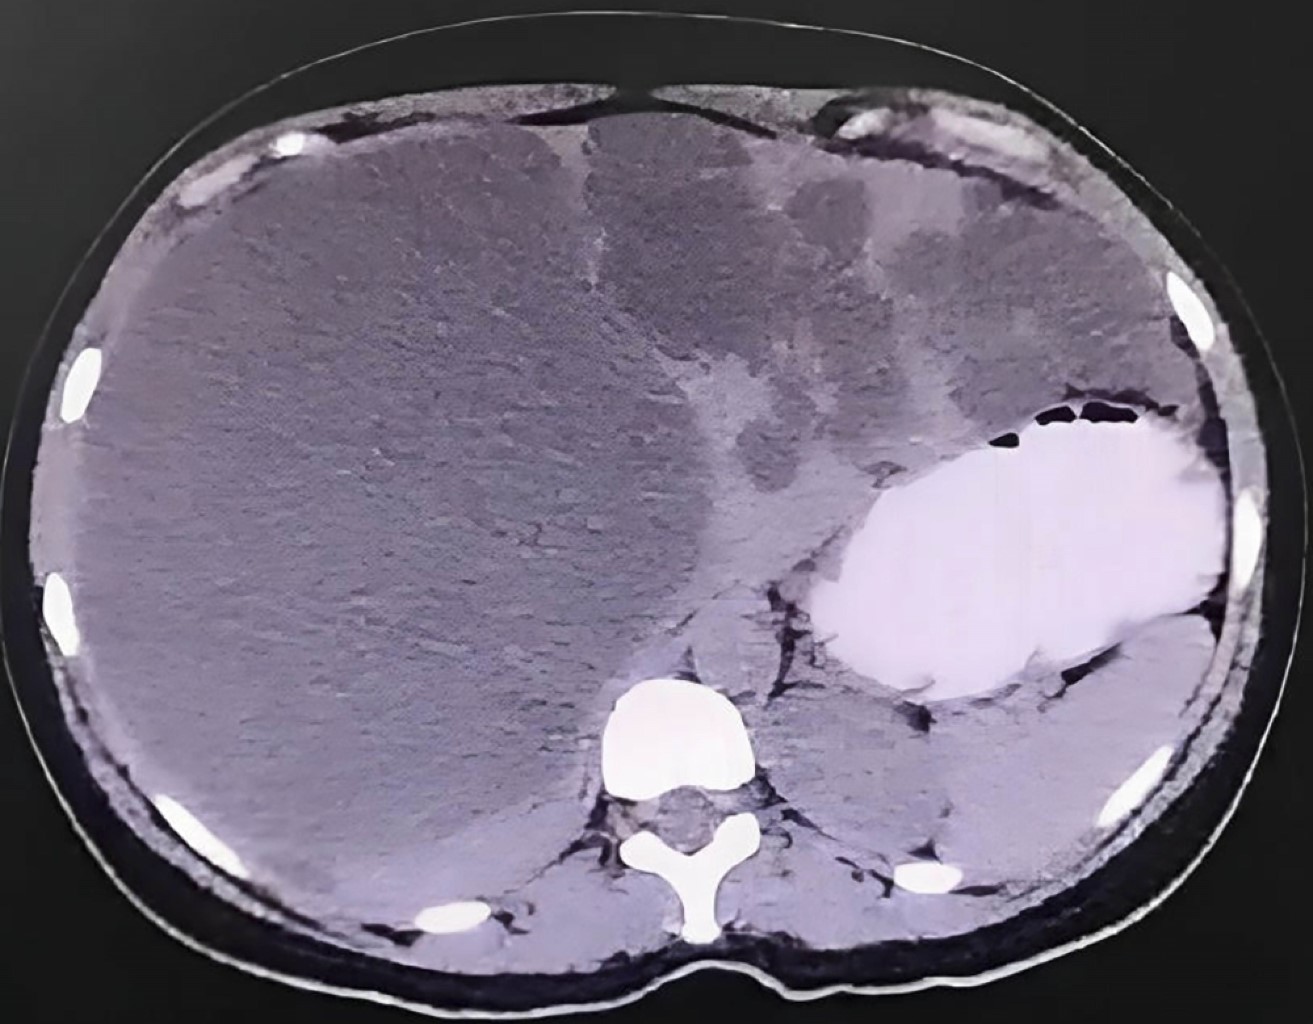

Polycystic liver disease: a case report with laparoscopic intervention

Introduction: polycystic liver disease is a rare hereditary condition which makes up 3% of benign liver lesions that results in liver cysts due to mutations in fluid transport proteins and hepatic epithelial cell growth. Rarely, it occurs in isolation without polycystic kidney disease, which has a prevalence of 0.05 to 0.13%. Clinical case: a 31-year-old female with no relevant medical history presented with a 5-month history of colicky abdominal pain in the right hypochondrium, nausea, asthenia, and adynamia. Ultrasound and computed tomography revealed multiple anechoic cysts throughout the liver parenchyma, occupying 50% of the right lobe (2,200 cm3), classified as Gigot III/Schnelldorfer type C. Renal cysts were ruled out. Laparoscopy was performed with cyst unroofing using diathermy (high-frequency currents) and aspiration of 2,300 cm3 of citrine content, without postoperative complications. The patient was discharged two days later and, at one-month follow-up, showed complete resolution of symptoms. Conclusions: polycystic liver disease is a progressive genetic condition requiring treatment in a small number of cases. Supportive management is recommended for mild symptoms, and surgical treatment for moderate or severe cases. Here we successfully treated the patient using laparoscopy and cyst unroofing.

Figure 2